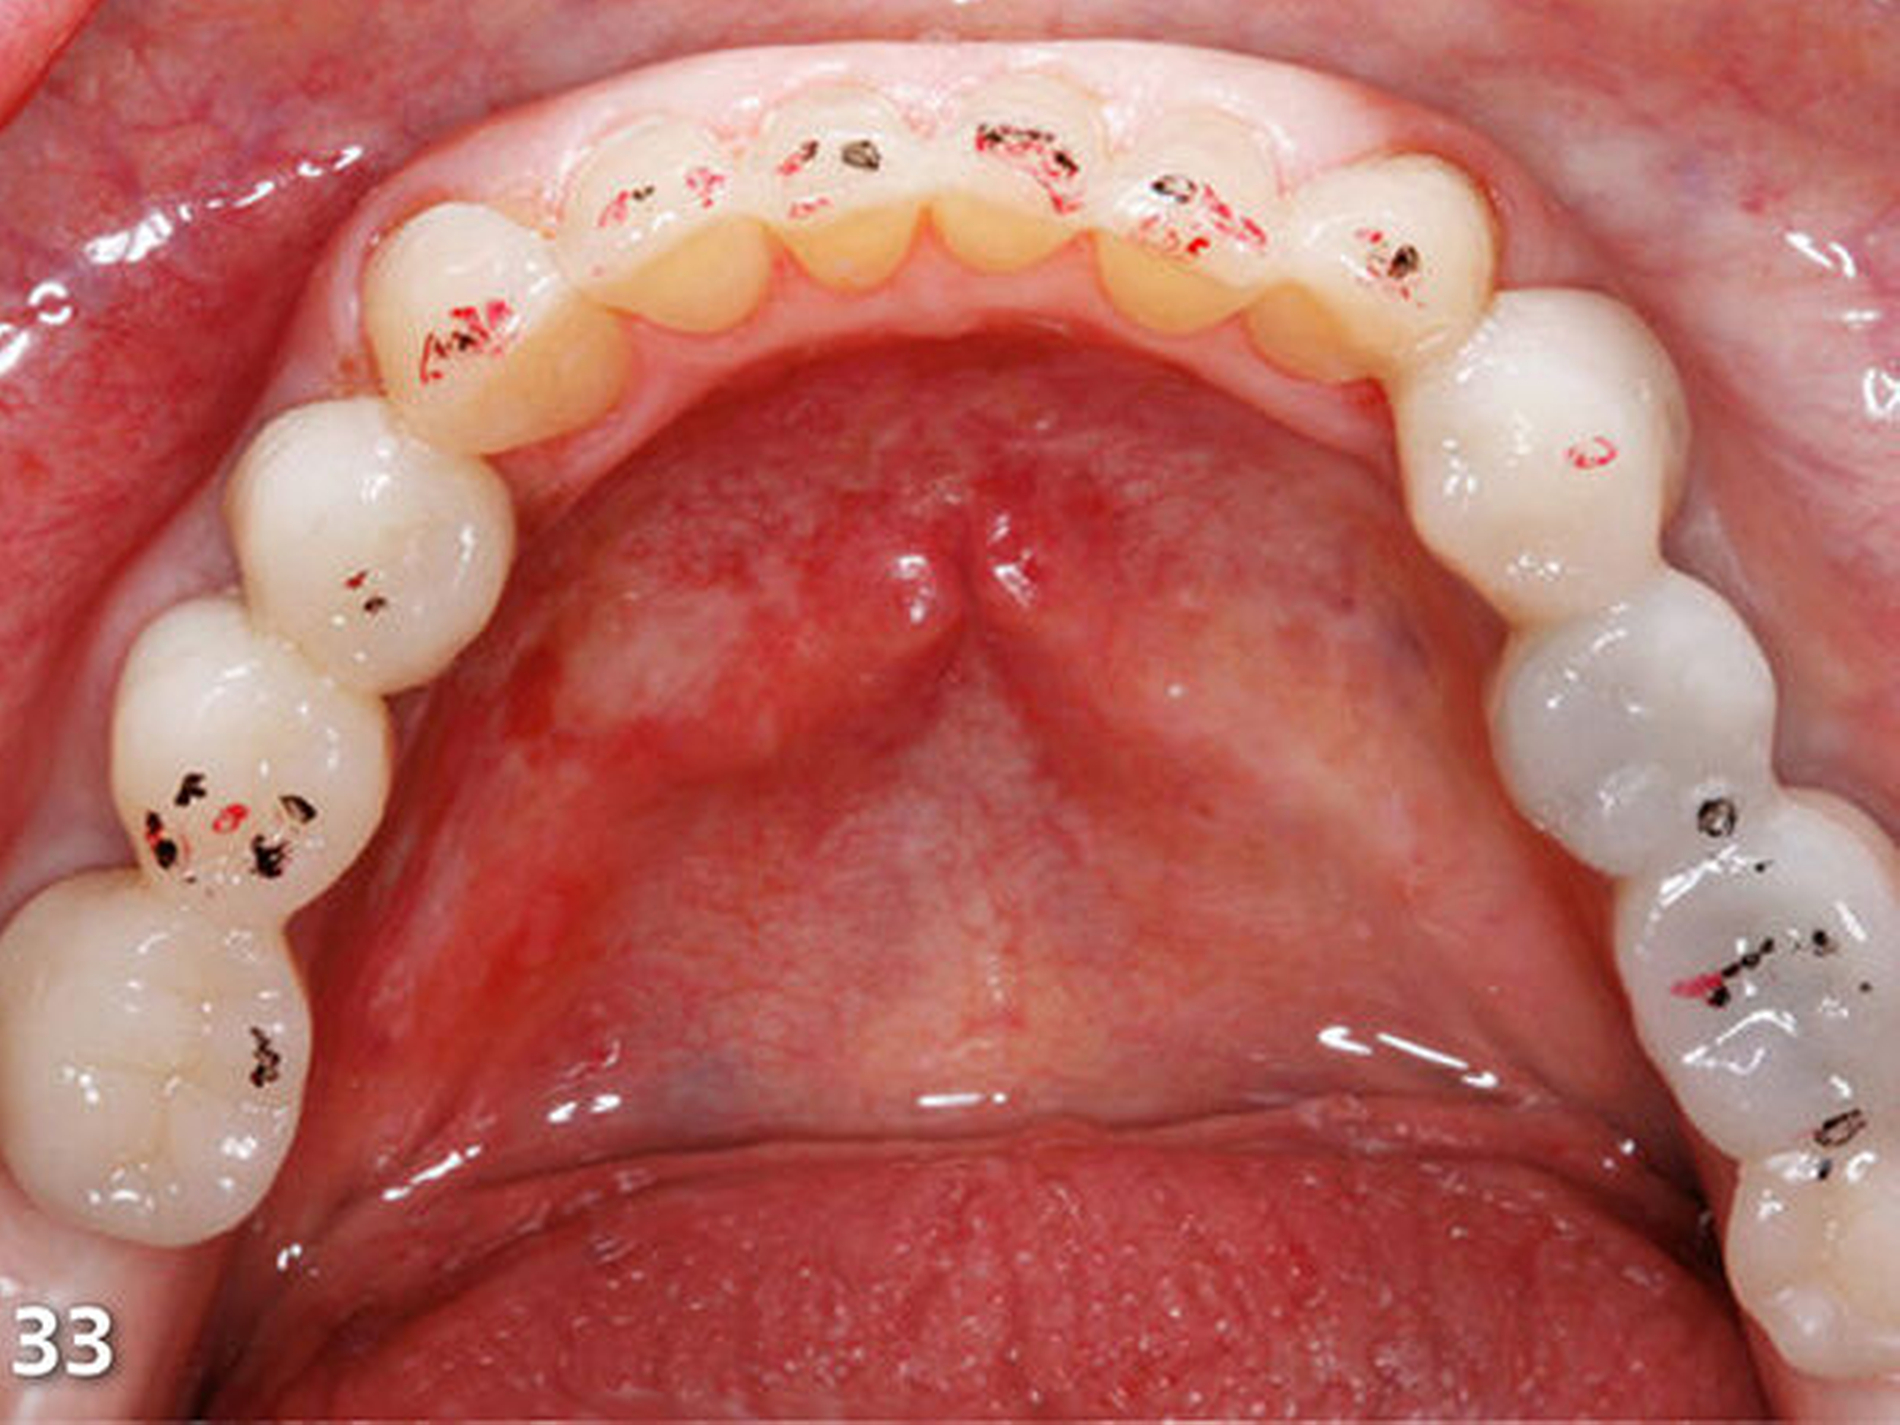

Nach dem Ausarbeiten und Polieren sämtlicher Restaurationen (Abb.31 und 32) wurden die statische und die dynamische Okklusion nochmals kontrolliert; es zeigte sich eine gute Übereinstimmung mit dem okklusalen Kontaktmuster aus dem Wax-up (Abb.33). Da sämtliche Restaurationen ohne Verabreichung von Lokalanästhesie aufgebaut wurden, konnte die Patientin sofort nach Abschluss der Behandlung, nach einer kurzen Phase der Lockerung der Kaumuskulatur, ein erstes positives Feedback zur neuen Unterkieferposition geben (Abb.34 und 35).